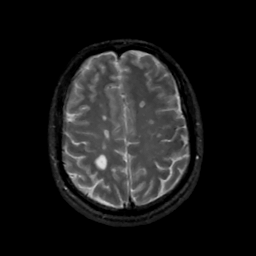

MR Study #14, June 2, 1991 -- Slice #37

[Home][Help][Clinical][Tour 1][Tour 2] Slice 37